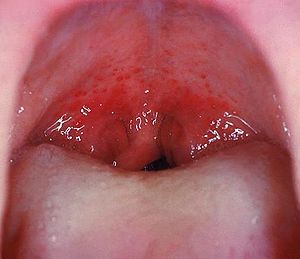

Small red spots on the soft palate in Strep throat

Forchheimer spots are a type of enanthem seen as tiny red spots on the soft palate in rubella, measles and scarlet fever.[1] They sometimes precede the skin rash of rubella.[1]

The spots may be present in around 20% of people with rubella.[1] The sign is named after Frederick Forchheimer.[2]